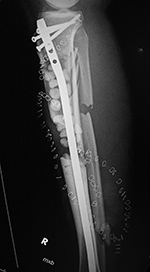

| 43 year-old man with comminuted right tibia and fibula fractures as well as extensive bone loss and soft tissue injury. A tibial intramedullary nail with proximal and distal locking screws is present as well as multiple rounded bony allografts. There are also large skin staples. |